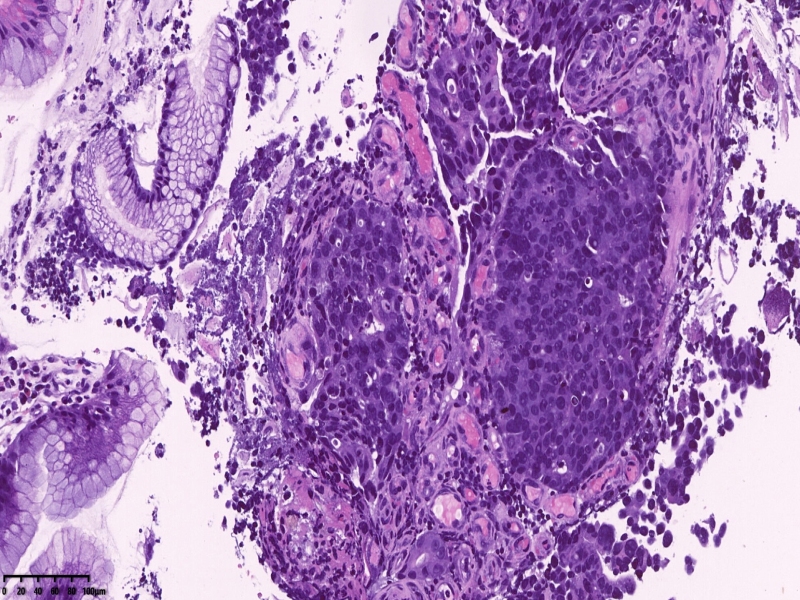

镜下所见:胃粘膜组织数块,炎症背景,其中3块固有层内可见细胞团,瘤细胞排列呈条索状迂回后呈巢状,巢的边缘瘤细胞呈栅栏状。细胞形态似柱状。

第一感觉考虑神经内分泌肿瘤?会诊考虑低分化腺癌。以前也遇到一个类似病例,贲门口占位,初步考虑神经内分泌肿瘤,但是神经内分泌标记均为阴性,最后考虑低分化腺癌。